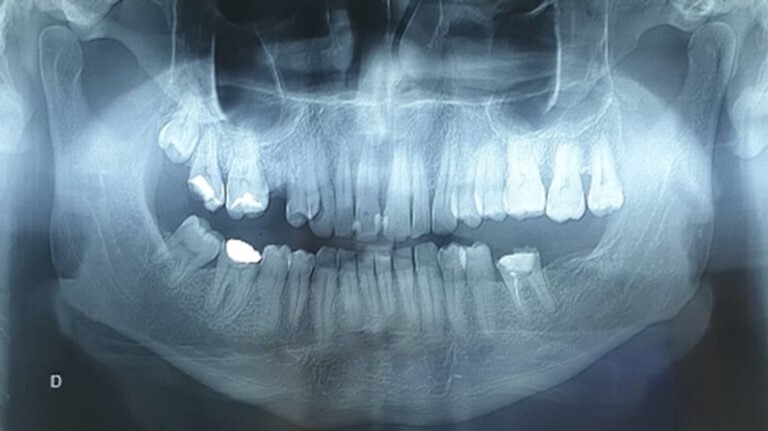

罗赛-多夫曼病(RDD)由 J Rosai 和 R F Dorfman 于 1969 年首次描述,是一种病因不明的良性、自限性组织细胞增生症。它通常出现在生命的头二十年。最常见的临床表现是无痛性双侧颈淋巴结病,伴有发热、体重减轻和血沉增快。然而,无结节受累的 RDD 极其罕见,最常见的结节外部位是头颈部,主要累及鼻腔、咽部和副鼻窦。口腔部位的罗赛-多夫曼病偶见;据我们所知,文献中仅发现 17 例无淋巴结受累的口腔罗赛-多夫曼病。由于这些孤立的口腔表现非常罕见,因此需要对其临床和放射学方面进行更多的研究。本文旨在介绍一例罕见的无淋巴结受累的口腔罗赛-多夫曼病病例,详细介绍其临床和影像学表现,以及对我们的患者所采用的治疗策略。

First described by J Rosai and R F Dorfman in 1969, Rosai-Dorfman disease (RDD) is a benign, self-limiting histiocytosis of unknown etiology. It is usually seen in the first two decades of life. The most frequent clinical presentation is painless, bilateral cervical lymphadenopathy accompanied by fever, weight loss, and an elevated ESR. However, RDD without nodal involvement is extremely rare, and the most common extranodal location is the head and neck region, mainly affecting the nasal cavity, pharynx, and paranasal sinuses. Oral location of RDD is occasional; according to our knowledge, only 17 cases of oral Rosai-Dorfman disease without lymph node involvement have been found in the literature. Because of the rarity of these isolated oral presentations, the clinical and radiological aspects need to be more studied. This article aims to present a rare case of oral Rosai-Dorfman disease without nodal involvement, detail the clinical and radiological signs, and the treatment strategy used in our patient.